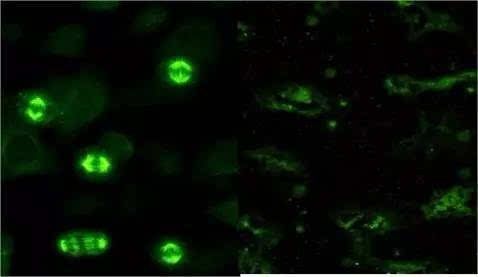

免疫荧光是一种利用抗原-抗体反应进行细胞或组织中抗原物质定位的技术。它利用荧光染料标记抗体,使其与特定的抗原结合,然后通过荧光显微镜观察和分析荧光信号。免疫荧光主要用于研究细胞的结构和功能、检测生物分子间的相互作用以及疾病诊断等。

FISH是一种基于荧光原位杂交技术的核酸探针检测方法。它利用特定的核酸探针与细胞中的DNA或RNA序列进行杂交,然后通过荧光显微镜观察和分析荧光信号。FISH主要用于检测基因或染色质异常、染色体变异等遗传学问题,也可用于肿瘤诊断和预后评估等。

免疫荧光的观察和分析主要通过荧光显微镜进行,可以观察荧光的颜色、亮度、分布等信息,从而对细胞或组织的结构和功能进行分析。

FISH的观察和分析同样通过荧光显微镜进行,可以观察探针与目标序列的杂交情况以及荧光信号的强度和分布,从而对染色体变异、基因表达等问题进行分析。